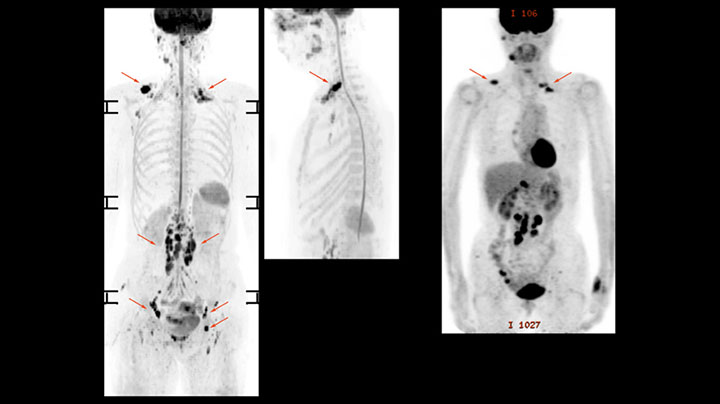

A 61-year-old female with a malignant lymphoma underwent an MRI exam with whole body diffusion weighted imaging (DWIBS) as well as PET. On the images shown, the resolution of DWIBS is better than PET, which allows visualization of the small pelvic lesions and almost no distortion is seen in the neck area.